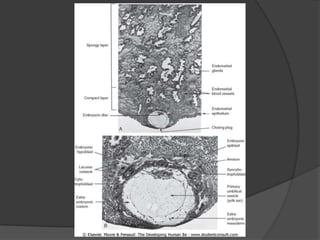

Durante a segunda semana, o tampão cobre o epitélio do endométrio, o sinciciotrofoblasto produz hCG, e forma-se a cavidade amniótica e o embrioblasto. O mesoderma extraembrionário forma o saco vitelino definitivo e o celoma extraembrionário, enquanto o saco coriônico desenvolve vilosidades coriônicas. Ao fim da semana, a placa pré-cordal se forma.